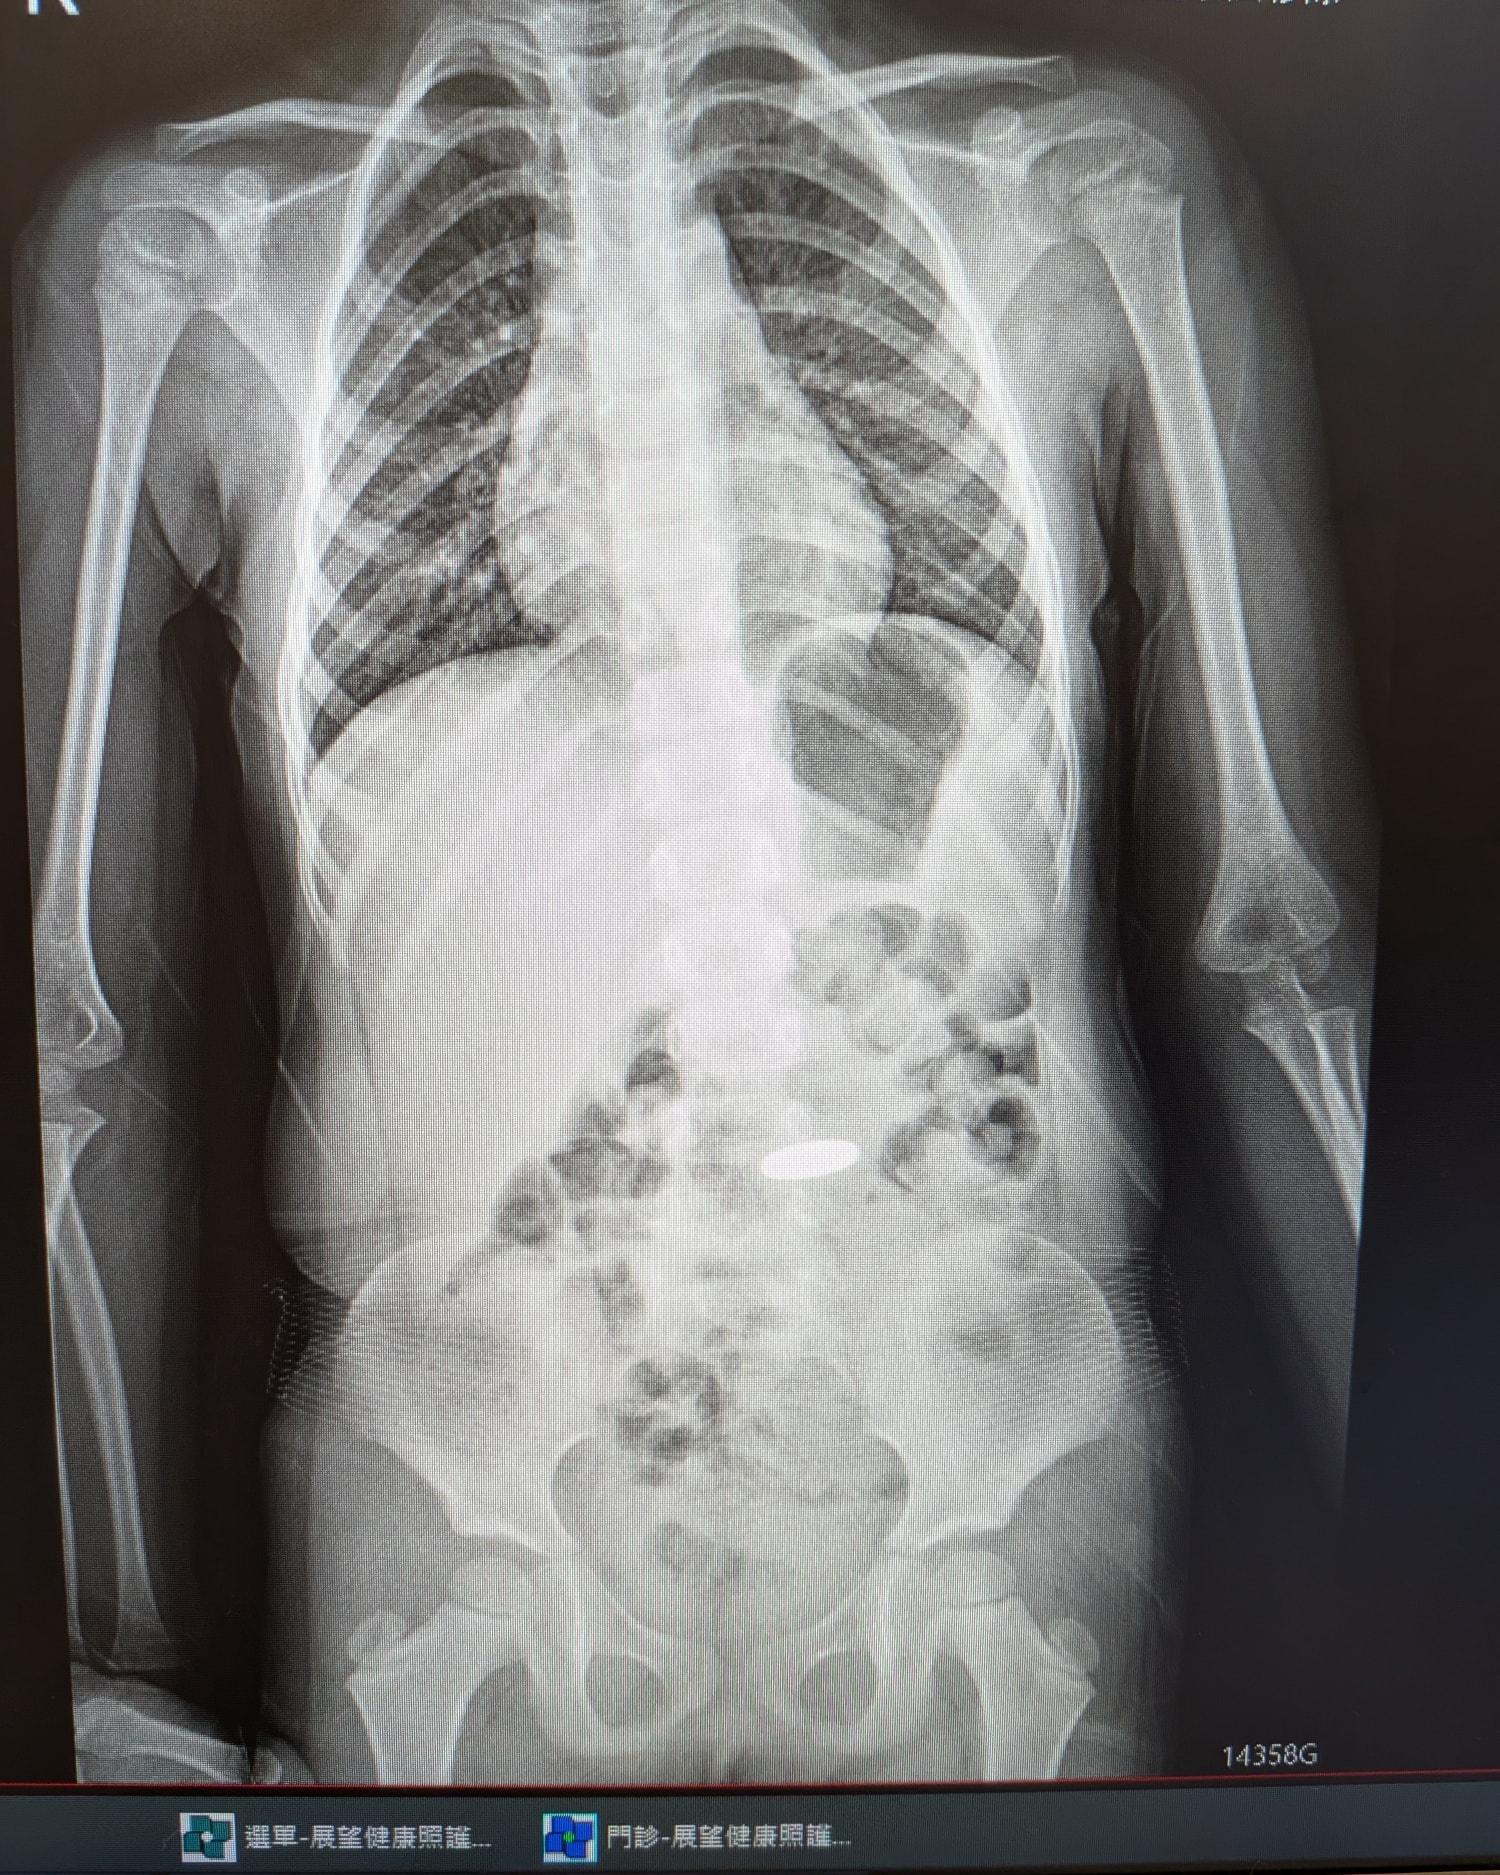

今天小孩回診,我也順便上雲端系統看看硬幣在哪兒,幸好硬幣已經通過食道![]()

如果 1 元硬幣已經通過食道、進到胃裡,在孩子沒有症狀的情況下,通常會隨著腸胃蠕動自行排出;很多孩子會在2–3 天內排出,但也可能需要幾天到數週(甚至到約 1 個月)才排出。

如果硬幣卡在食道(最常卡的地方之一),就不一定會自己掉下去,可能需要醫療處置;因此通常建議用 X 光確認位置,這也是臨床指引強調的處理重點之一。